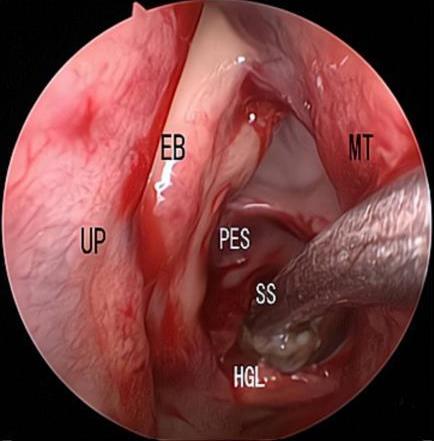

• 内镜下经中鼻甲基板入路四步程序化开放蝶窦的疗效分析

摘要:目的 探究经中鼻甲基板入路的手术技巧及临床效果,旨在系统评估一种兼具良好手术视野和微创性的蝶窦开放径路。方法 回顾性分析2019年9月-2023年9月该院收治的35例孤立性蝶窦病变或单侧蝶窦伴毗邻筛窦受累患者的临床资料,均经中鼻甲基板入路的“四步”程序化操作开放蝶窦。观察手术相关情况和并发症发生情况;采用视觉模拟评分法(VAS)评分,评估头痛和流涕等症状改善情况;采用改良隆德-肯尼迪(MLK)评分,评价术腔恢复状况。结果 所有患者术中保留钩突、中鼻甲和筛泡,26例(74.3%)保留上鼻甲;所有患者均达到临床治愈标准,表现为:术腔引流通畅,黏膜完全上皮化,以及蝶窦开口维持良好开放状态。术后病理显示:蝶窦霉菌病19例(54.3%),蝶窦息肉7例(20.0%),蝶窦黏膜慢性炎症9例(25.7%)。所有患者均未发生严重并发症,仅1例(2.9%)于术后12 d出现中鼻甲创面渗血,经电凝止血后治愈。头痛VAS评分由术前的(4.71±1.66)分,降至术后的(0.83±0.39)分,手术前后比较,差异有统计学意义(t = 13.71,P < 0.01);流涕VAS评分由术前的4.00(0.00,6.00)分,降至术后的0.00(0.00,1.00)分,手术前后比较,差异有统计学意义(Z = -4.47,P < 0.01);手术前后嗅觉减退VAS评分比较,差异无统计学意义(P > 0.05)。MLK评分由术前的4.50(2.00,4.00)分降至1.00(0.00,1.00)分,手术前后比较,差异有统计学意义(Z = -5.20,P < 0.01)。结论 经中鼻甲基板入路蝶窦开放术,严格遵循鼻窦解剖层次,在最大限度地保留鼻腔生理结构的前提下,可获得理想的术野暴露。该术式对于局限于蝶窦及后组筛窦的病变,具有确切的临床疗效。值得应用于临床。